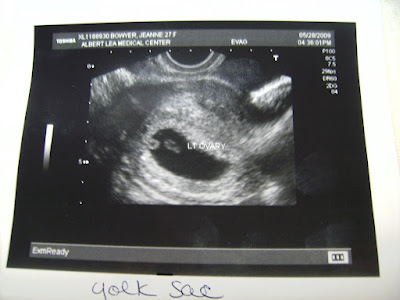

Soon we were underway and looking about. The first thing Dr T sad was "well, you're certainly pregnant". Then I saw out bean and said "Oh! Look! There it is! God, I hope it has a heartbeat! Please have a heartbeat..." to which he replied "Oh yes, it's got a heartbeat".

Anyhow. We zoomed in a bit on the bean, and sure enough, there was the beat, flickering away...

He explained all about the yolk sac - said it was lovely and round and that they'd be worried if it were crescent shaped.

Then we took measurements of the bean...1.3cm and right on 7 weeks, 3 days! Growing away!

The best part of the whole visit was, by far, seeing that magical little heartbeat on screen and listening to the steady "whauff, whauff, whauff". I told both Dr T and Nurse A that the last time I'd seen an ultrasound there hadn't been a heartbeat on it. To see a heart beating inside me was just incredible. I love to see life perservering like this. It just does continue, it does, if you let it...